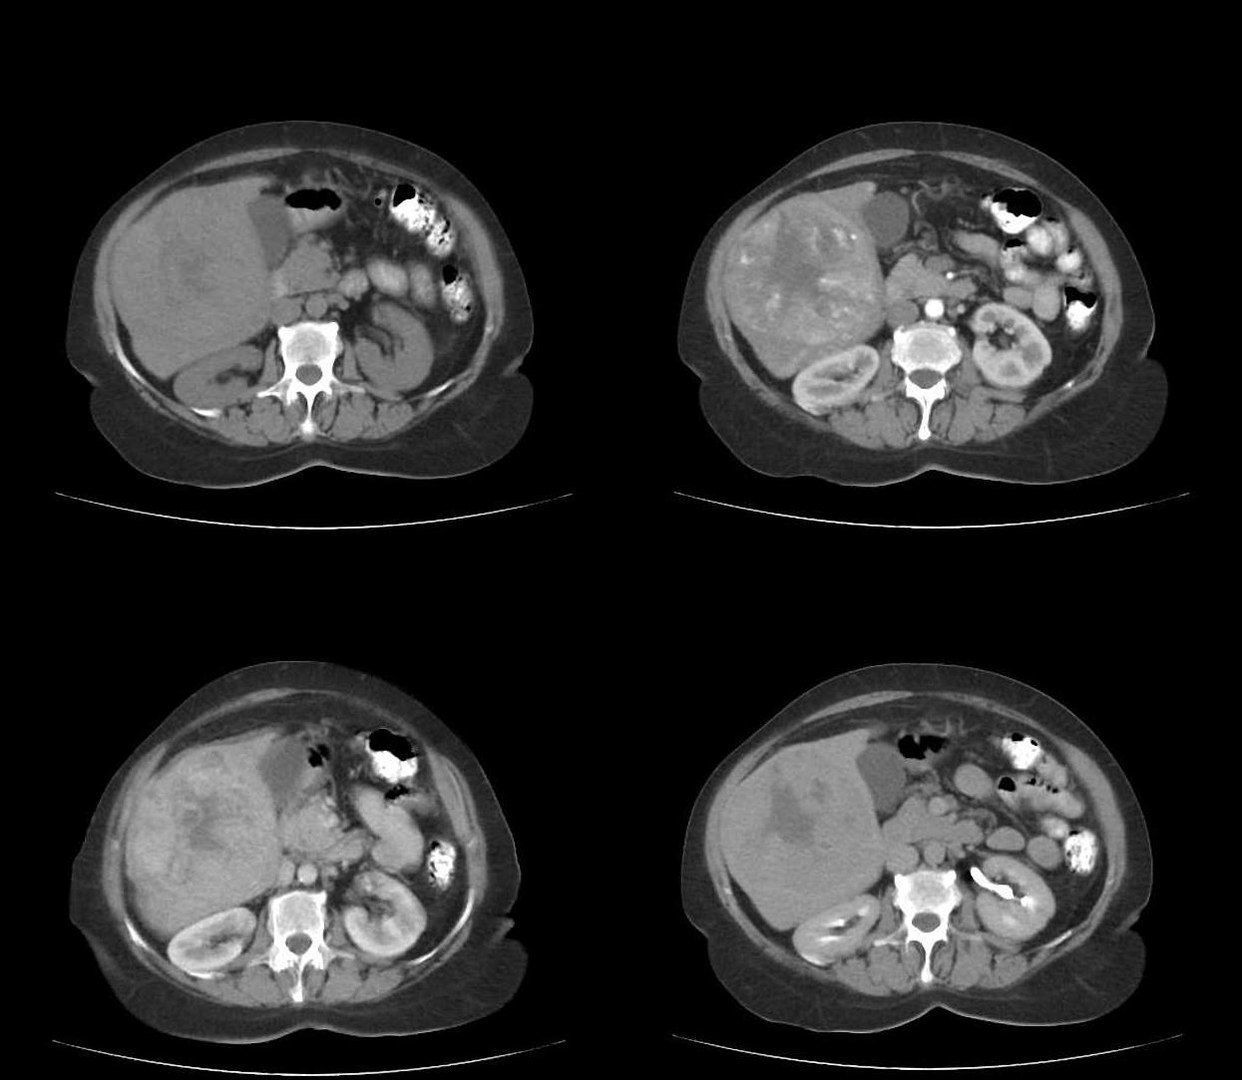

Методы динамического контрастирования печени на МРТ

Раздел: Снимки-подсказки